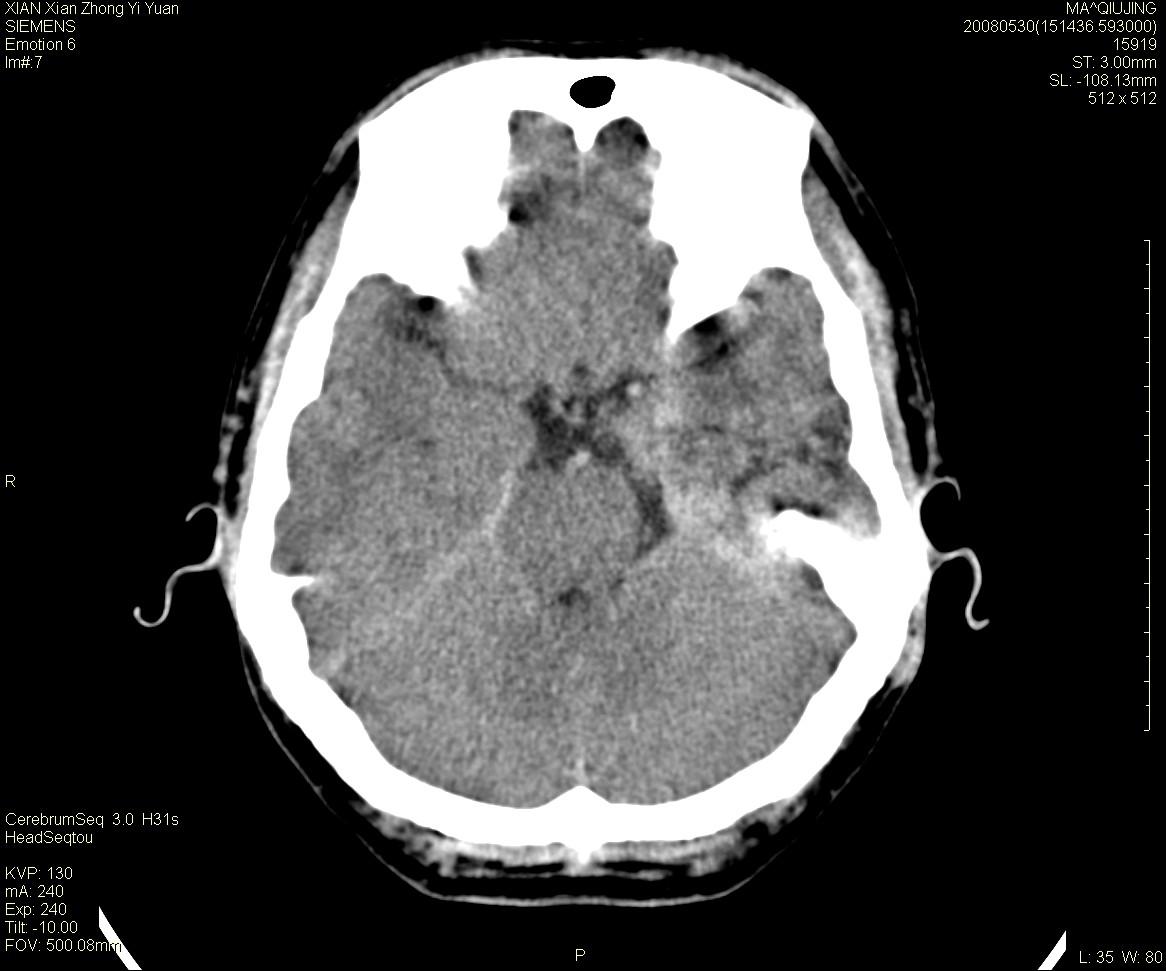

标题: CT13768:少见病例,血管畸形。

患者m47,头晕数年,没给强化,让做dsa去了。

avm

第一感觉:avm,但其中更低密度区不清楚,好像有脂肪密度,胆脂瘤破裂?

avm,低密度区应该是以前出血过的液化灶

血管畸形,支持,如果增强扫描,则可见粗大,迂曲血管团。